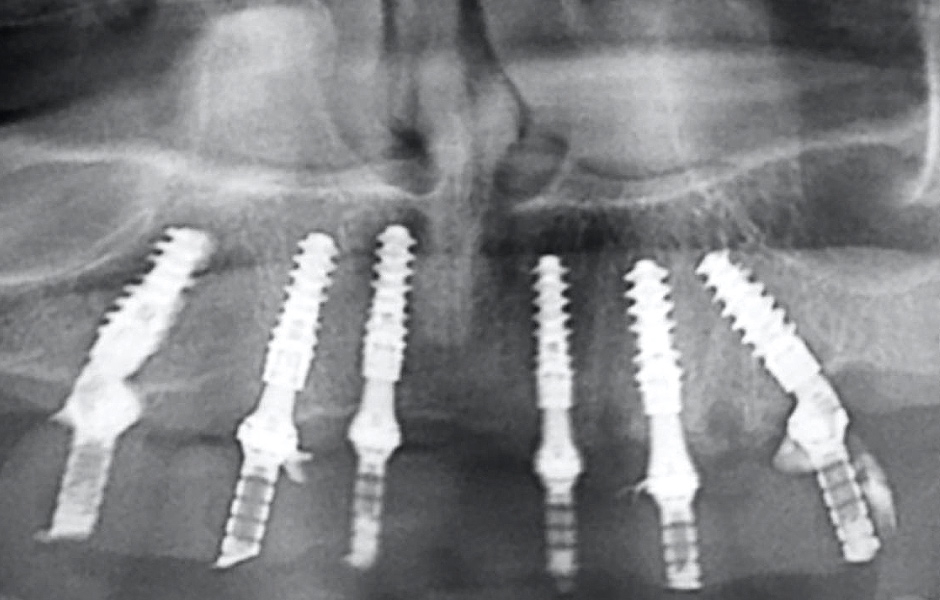

Kontrolní rentgenový snímek potvrdil, že jsou všechny klinické parametry v normě (obr. 43).

Definitivní náhrada byla nasazena a ověřena z hlediska estetiky, okluze a funkce (obr. 51–55). Panoramatický kontrolní snímek potvrdil, že všechny parametry protetického ošetření odpovídají očekávaným hodnotám (obr. 56).

Obr. 43

Obr. 56